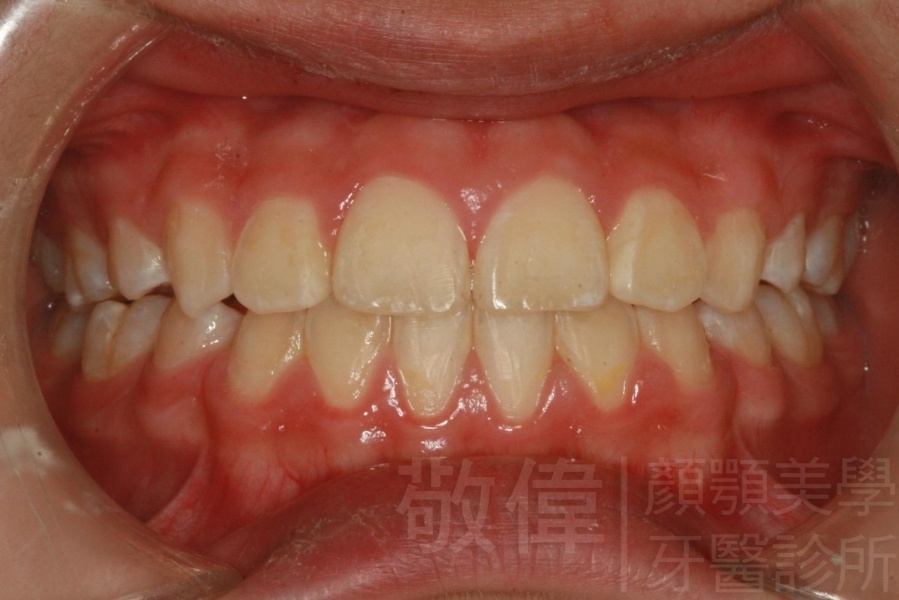

齒顏矯正/上顎暴牙且牙齒極度混亂

矯正前-右   矯正前-正   矯正前-左

矯正後-右   矯正後-正   矯正後-左

<個案說明>

上顎暴牙且牙齒極度混亂,經由矯正之後,臉型大幅度改善,牙齒的排列更加的整齊健康。相較於之前眼神充滿精神,自信心展現無遺。